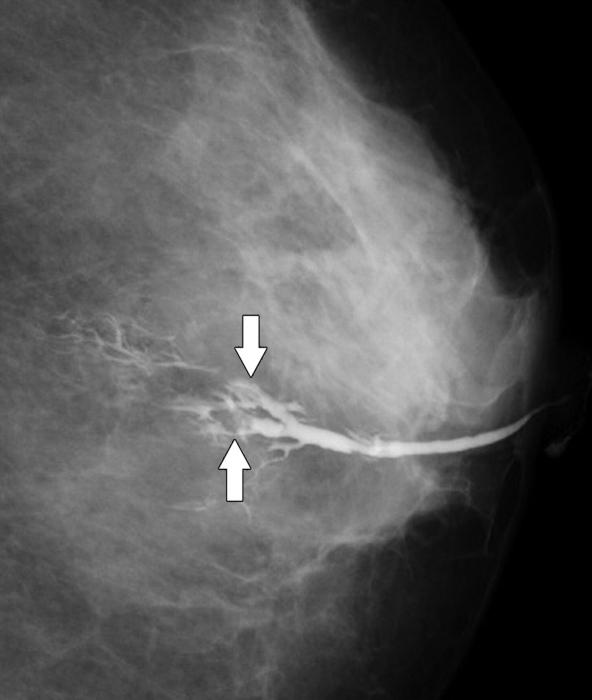

- маммография – комплексное исследование молочной железы;

- дуктография – рентгенологическое исследование молочных желез, во время которого в их протоки вводят контрастное вещество, а затем делают рентгенологические снимки;

- рентгеновская маммография – делают рентгенологические снимки в нескольких проекциях;